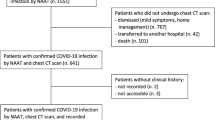

In the development cohort (from 3 university hospitals in Bordeaux, Grenoble, and Montpellier and a private hospital in Bordeaux, France), patients were eligible if they were at least 18 years old, and had a first chest CT performed without injection of contrast agent for respiratory symptoms which led to highly suspicious or compatible according to standardized visual analysis of COVID-19. Besides, they should have either a biological diagnosis (RT-PCR) or a clinical suspicion (cough and/or dyspnea and/or fever and/or need to use oxygenotherapy as part of routine care) of COVID-19 at the time of the CT scan, between March 1, 2020, and May 5, 2021 (Figure S1). Non-inclusion criteria were patients with moderate or severe forms (defined as oxygenotherapy ≥ 3 L/min to obtain a SpO2 > 97%) or critical forms of COVID-19 (defined by the need for non-invasive or invasive ventilation and/or orotracheal intubation) on the date of the first chest CT. In the validation cohort (university hospitals in Nancy and Poitiers, France), eligibility criteria were similar, except that half of the patients had chest CT with a contrast agent injection.

Validation cohort

A total of 827 participants were included in the development cohort (Fig. 1). The study demographics are presented in Table 1 and Table S3. Briefly, mean age was 65.5 [IQR 54; 79] years; there were 495 (59.9%) men, with a median BMI of 27.4 [23; 30] kg/m2 and a median time between first symptoms and CT of 6 [2; 10] days. Comorbidities were mainly hypertension (373, 45.1%), obesity (178, 21.7%), and diabetes mellitus (170, 20.6%). Asthma and COPD affected respectively 9.3 and 8.5% of the population. A positive RT-PCR during the acute phase was reported for 461 (64.8%) participants. Mean lymphocyte level was 1.16 ± 1.35 G/L, CRP 86 ± 82 mg/L. CT features were distributed as follows: ground-glass opacities affecting 805 (97.3%). The extent of the COVID-19 suspected lesions were mild (182, 22.0%), moderate (389, 47.0%), extended (200, 24.2%), severe (52, 6.3%), or critical (4, 0.5%). Finally, 440 (53.2%) participants were graded highly suspicious for COVID-19 diagnosis, the others being compatible.

Baseline characteristics and outcomes of the external validation cohort